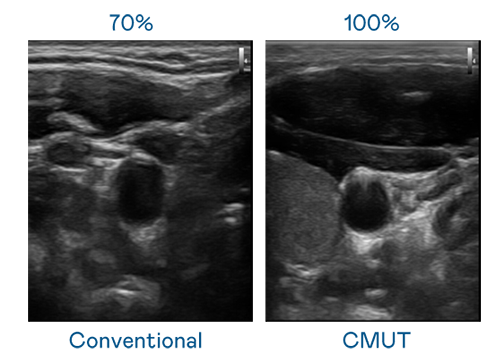

CMUT 技术是一种用电容式微机电元件来产生超音波讯号的技术。与传统 PZT 压电式技术相比,CMUT 频宽增加 30%,更宽频的超音波讯号让影像解析度大幅提升,是实现高影像品质医疗超音波扫描、促进精准医疗发展的关键技术。

超音波影像的解析度高低,首先取决于探头能发出的讯号频宽。AG公司 CMUT 可提供高清晰的超音波讯号,提供高频宽、高灵敏度、影像纹理细节更高的超音波影像,协助医护人员缩短影像判读时间及利用精准的医疗影像进行诊断。